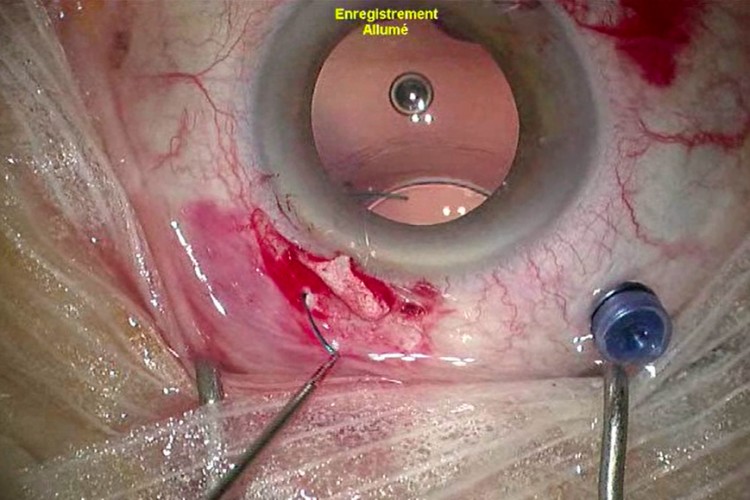

Greffe cornée Carlevale